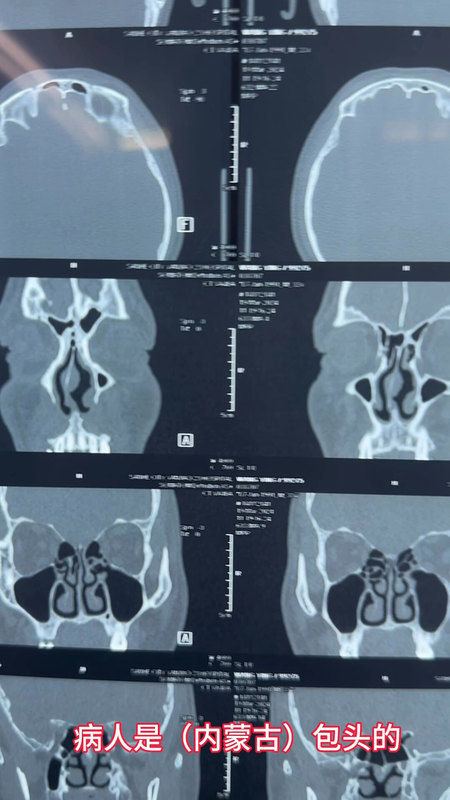

一、診斷方法?●??前鼻鏡檢查?:初步觀察鼻腔結(jié)構(gòu)?!??鼻內(nèi)鏡/CT掃描?:精確評(píng)估偏曲位置和程度,CT為金標(biāo)準(zhǔn)?!??過敏或功能測(cè)試?:排除其他病因(如過敏性鼻炎)。二、治療方式?1.??保守治療?:a.??鼻噴激素?(如布地奈德):減輕黏膜腫脹。b.??抗組胺藥?:緩解過敏癥狀。c.??生理鹽水沖洗?:保持濕潤,減少結(jié)痂。d.??短期減充血?jiǎng)?:避免長期使用導(dǎo)致藥物性鼻炎。2.??手術(shù)矯正(鼻中隔成形術(shù))?:a.??適應(yīng)癥?:嚴(yán)重影響生活或并發(fā)癥(如頑固性鼻竇炎)。b.??術(shù)式?:黏膜下切除或重建術(shù),保留軟骨支撐結(jié)構(gòu)。c.??風(fēng)險(xiǎn)?:出血、感染、穿孔(<1%)、復(fù)發(fā)(5%-10%)、短暫鼻部麻木。三、術(shù)后護(hù)理要點(diǎn)?●??避免擤鼻/碰撞?:至少2周,防止出血?!??濕潤鼻腔?:生理鹽水噴霧+凡士林涂抹,加濕器輔助?!??定期復(fù)查?:清理血痂,監(jiān)測(cè)愈合?!??活動(dòng)限制?:1周內(nèi)避免劇烈運(yùn)動(dòng),2周內(nèi)禁煙酒?!??疼痛管理?:按醫(yī)囑用藥,避免阿司匹林類抗凝藥。

鼻塞4年,原來是這個(gè)問題,總算解決了

最近來自廣東佛山禪城的梁先生,38歲,鼻塞4年了,用了不少的藥,但是沒多大效果,非常的影響睡眠和心情。沒辦法,這次特意來找耳鼻喉鄭立崗醫(yī)生想徹底的治愈自己的鼻塞。做了鼻竇CT檢查后發(fā)現(xiàn)原來鼻中隔有嚴(yán)重的偏曲,這種情況是結(jié)構(gòu)性的問題,一般來說吃藥是沒有多大效果的,需要手術(shù)治療才可以解決。入院后安排了鼻內(nèi)鏡下鼻中隔矯正+雙側(cè)下鼻甲射頻消融術(shù),插管全麻后就開始了手術(shù),在鼻內(nèi)鏡下通過鼻孔直接矯正偏曲的鼻中隔。射頻針消融肥大的下鼻甲,讓下鼻甲縮小。整個(gè)的過程持續(xù)約60分鐘,非常的順利。術(shù)后查房患者無明顯的不適,無手術(shù)相關(guān)的并發(fā)癥。對(duì)于鼻塞,如果您還有什么問題,歡迎留言和耳鼻喉鄭立崗醫(yī)生進(jìn)一步交流。